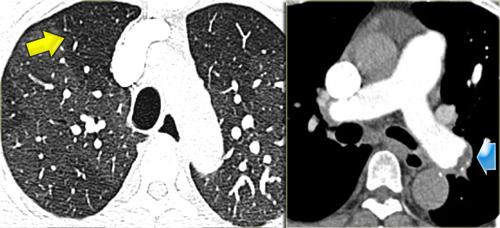

Ca lâm sàng minh họa: Ung thư lan tràn theo đường bạch huyết

Hình ảnh

Dày vách khu trú, không đều ở thùy trên phổi phải trên bệnh nhân có tiền sử ác tính đã biết. Dấu hiệu này điển hình cho ung thư phổi lan tràn theo đường bạch huyết.

Các đặc điểm hỗ trợ chẩn đoán bao gồm:

- Hạch bạch huyết trung thất

- Tổn thương dạng nốt ở phổi trái, nhiều khả năng là di căn.

Ung thư phổi lan tràn theo đường bạch huyết (PLC):

- Trong 50% trường hợp, dày vách có tính chất khu trú hoặc một bên, giúp phân biệt với các nguyên nhân khác (ví dụ: sarcoidosis, phù phổi do tim).

- Hạch bạch huyết rốn phổi có thể thấy trong 50% bệnh nhân, và thường có tiền sử bệnh ác tính.